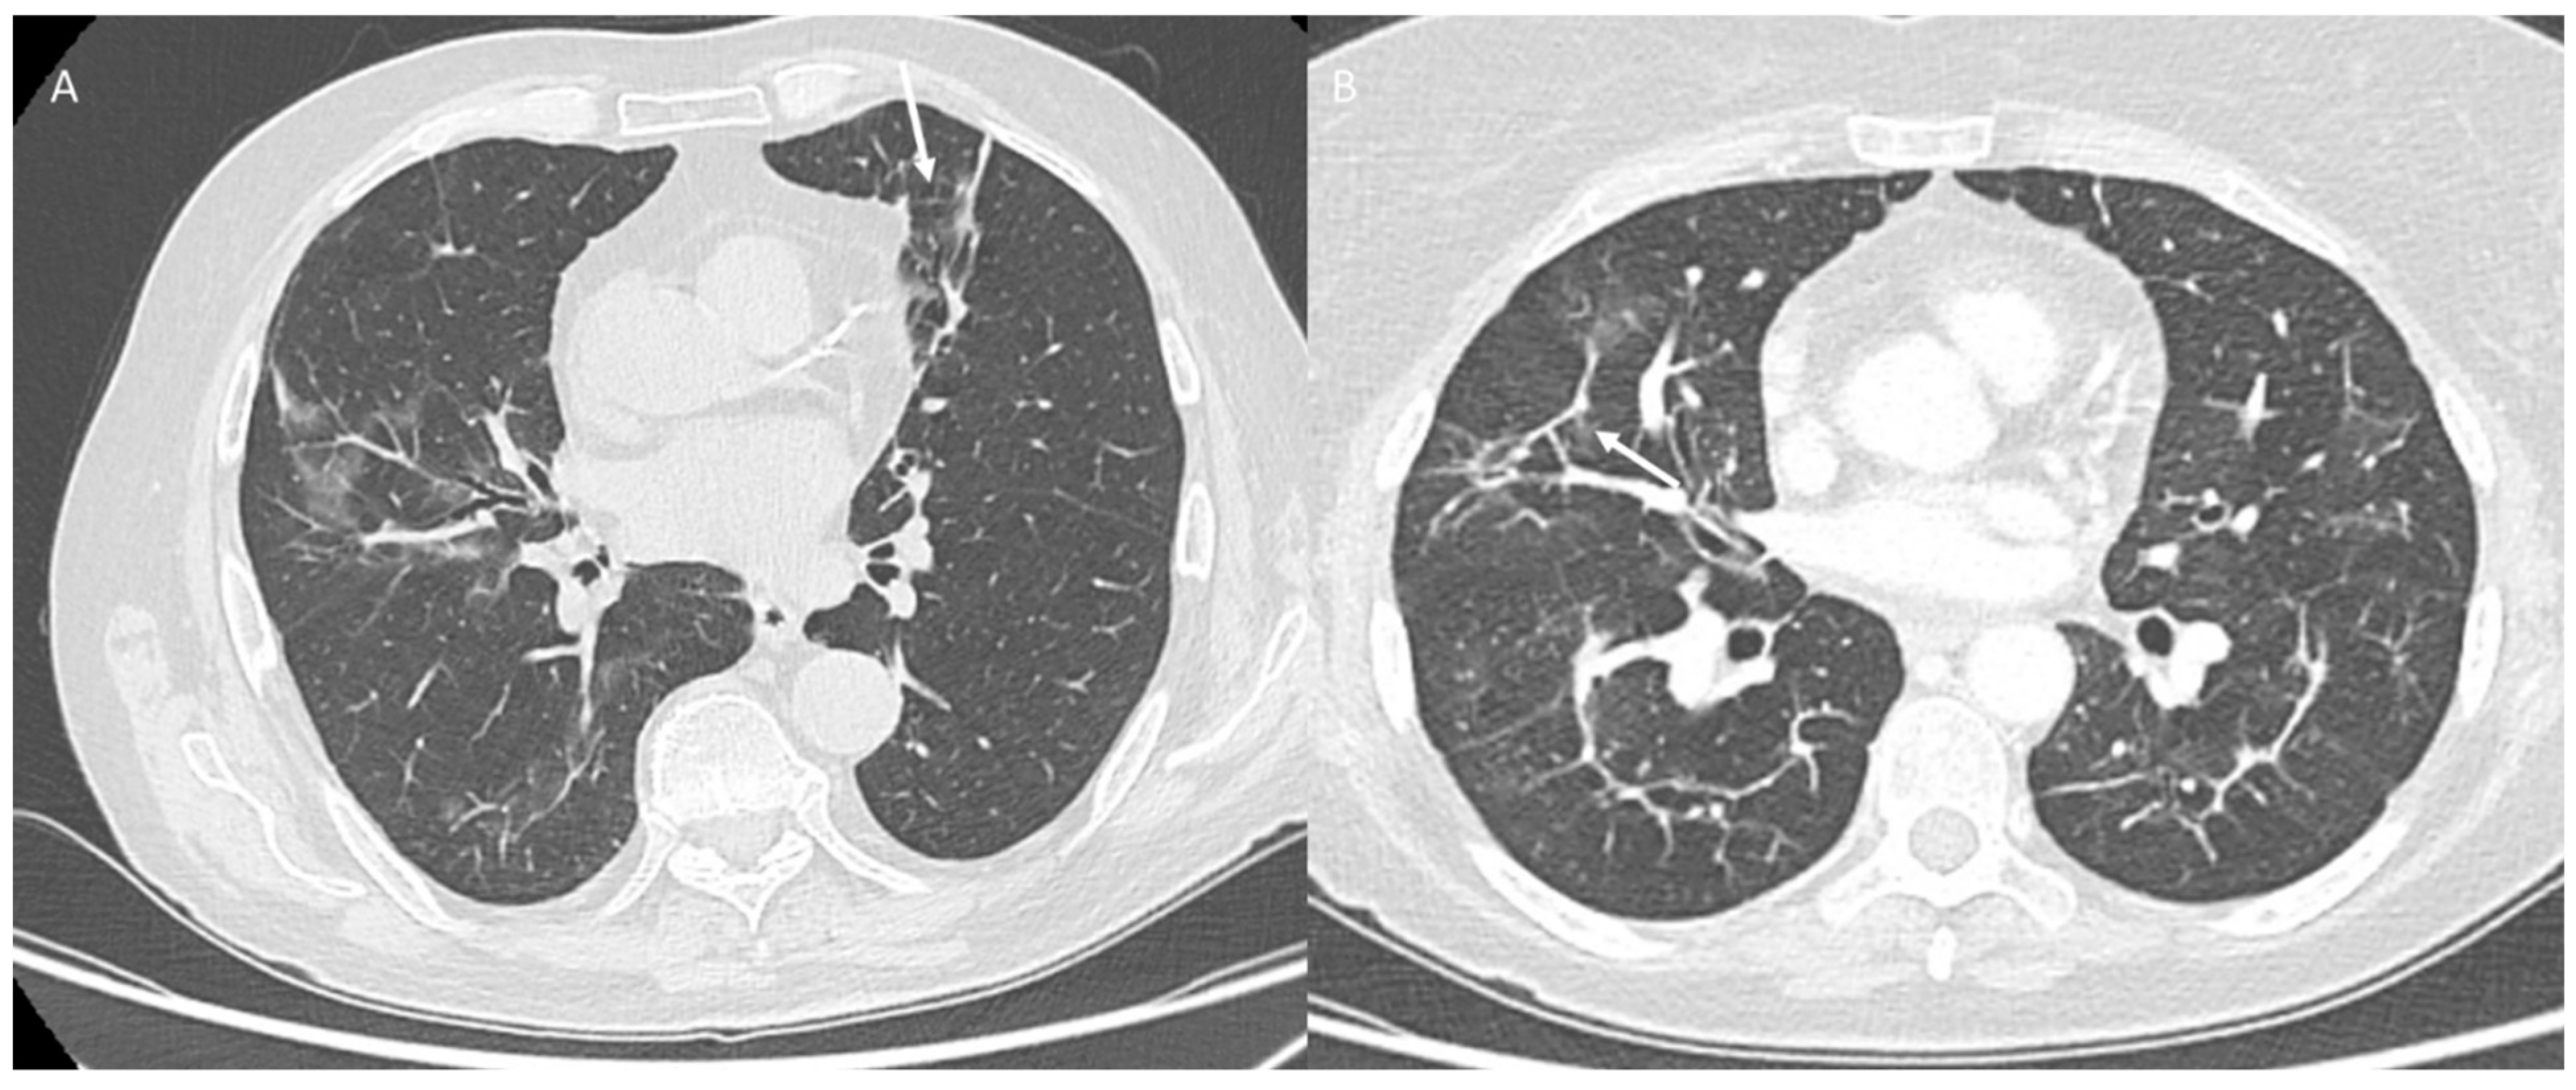

Compared to RT-PCR, the specificity of CT in detecting COVID-19 is lower, with an overall reported specificity of 46–80% [145,146,147]. This is due to the fact that the typical pattern of COVID-19 pneumonia shows a partial overlap with that of other lung diseases: ground-glass opacity (GGO), consolidation, crazy pavement, and enlargement of subsegmental vessels (diameter greater than 3 mm) in the GGO areas [148,149,150]. The temporal course of these anomalies was described by Pan et al., reporting four phases of the disease: initial stage (0–4 days after the onset of symptoms) with GGO as the main finding (Figure 5), progressive stage (5–8 days after onset of symptoms) with widespread GGO, mad pattern and consolidation, peak stage (9–13 days after onset of symptoms) with consolidation becoming more prevalent (Figure 6) and advanced stage (≥14 days after the onset of symptoms) with gradual absorption of anomalies (Figure 7) [151]. A recent study examined the performance of radiologists in differentiating COVID-19 from non-COVID-19 viral pneumonia, revealing an accuracy of between 60 and 83% [152].

Figure 6. COVID-19 patient at peak stage. CT (axial plane: (A,B)) shows consolidation (arrow).

Figure 7. COVID-19 patient at late stage. CT (axial plane: (A,B)) shows fibrotic-like changes (arrow).